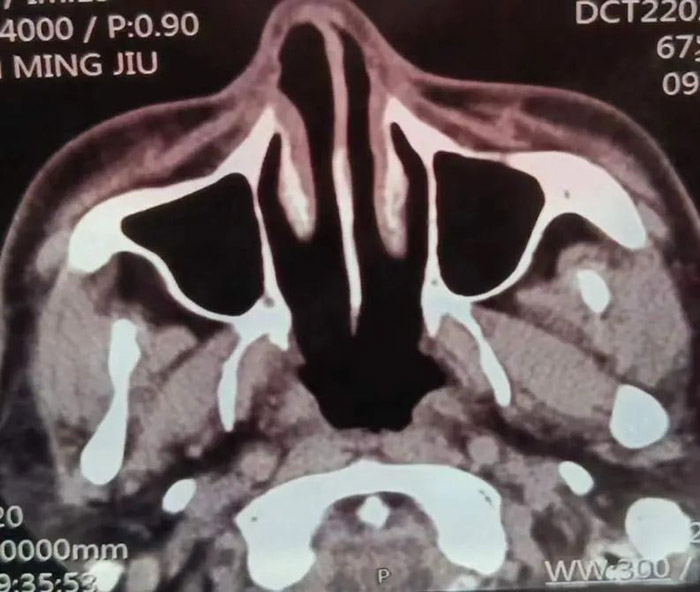

2021年7月,这是患病的第七年,范先生发现自己的右眼逐渐视物不清,原以为只是年龄的问题老花眼或眼疲劳。但是从眼球逐渐外凸后,他开始紧张起来。在家人的陪伴下,范先生来到我院检查病情。鼻咽部CT显示:鼻咽癌复发,PET/CT结果显示:筛窦蝶窦有浸润、鼻腔转移、眼球外凸系肿瘤变大外张导致。

经过专家组研究,制定了二次放疗的方案,并对放射治疗过程进行分期评估和监控,以便进行方案修改与调整。这次治疗采用了先进的TaiChiPro双模式放射治疗系统。随着治疗次数的增加,范先生明显感觉自己的症状逐渐减轻。接近一个疗程的时候,他的视力已经恢复了很多,眼球外凸也明显回缩,除味觉稍差,其它的症状都没有出现。出院后一个月复查,CT提示鼻咽癌及转移灶明显改善,眼球外凸症状消失。

二次放疗后的CT图像和右眼恢复情况